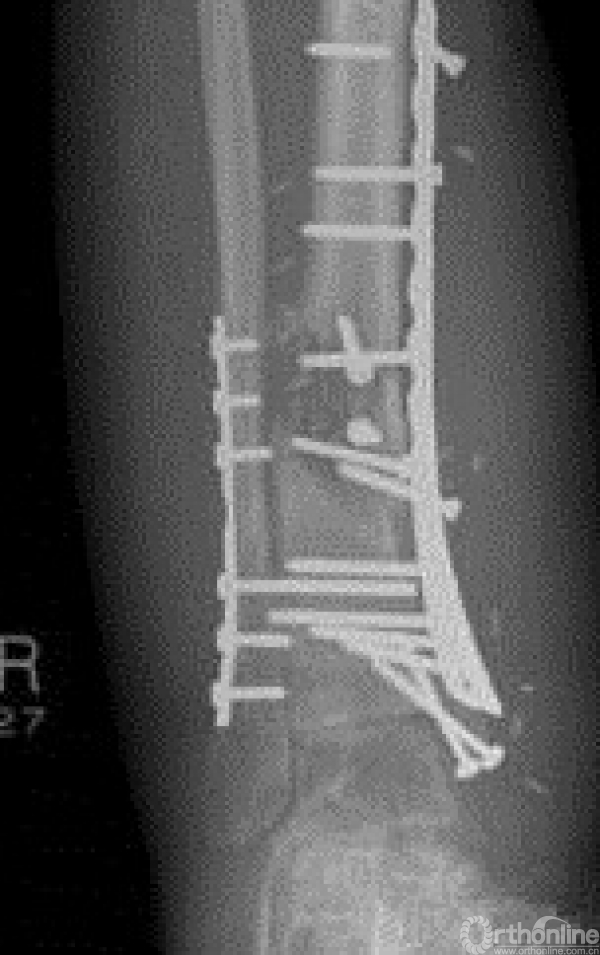

临床上常见反复发作,严重影响身心健康和劳动能力。急性骨髓炎起病时高热、局部疼痛,转为慢性骨髓炎时会有溃破、窦道形成、流脓、有死骨或空洞形成。重症患者可能会危及生命,有的不得不采取截肢的办法,致患者终生残疾。影像学和病理表现如下图。

5.外科处理去除死骨或异物以及脓性关节腔液引流极为重要。